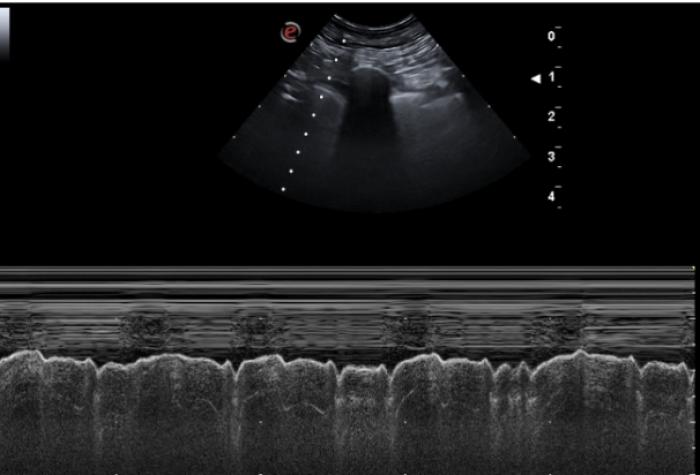

Ausencia de deslizamiento de la línea pleural

En todo pulmón aireado es vital la visualización del signo de deslizamiento (movimiento de izquierda a derecha originado por la movilización de la pleura parietal sobre la visceral).

La ausencia de dicho deslizamiento sumado a no visualizar el pulso pulmonar u otras alteraciones propiamente pulmonares como las líneas B, nos lleva al diagnóstico presuntivo de neumotórax. Ante esta sospecha intentaremos detectar el punto pulmonar (área sin signo de deslizamiento contigua a otra con deslizamiento visible) y anormalidades en el signo de cortina.

El signo de deslizamiento puede ser evaluado tanto en modo B como en modo M.

En caso de neumotórax severo con ocupación del receso costofrénico el signo de cortina se verá inalterado llamándose pseudo signo de cortina y siendo exactamente igual que el signo de cortina del paciente sano. En caso de neumotórax parcial, podemos ver el signo de cortina asincrónico, en el cual las vísceras abdominales se desplazan caudalmente en la inspiración y el signo de cortina lo hace cranealmente (al contrario que en el paciente sano) (Figura 8A-C).